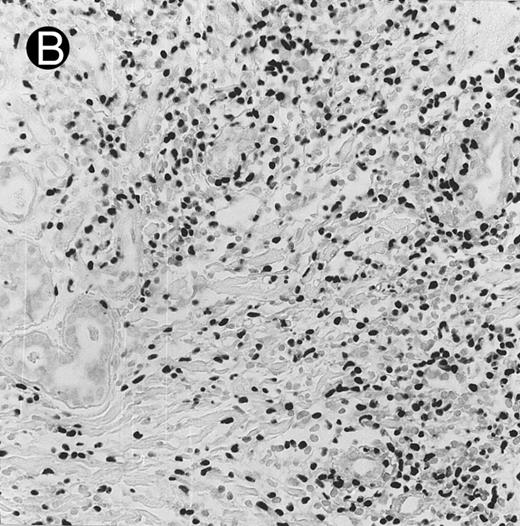

Blastoid NK cell lymphoma (case no. 40). (A) Biopsy shows a diffuse lymphomatous infiltrate with a prominent single-file pattern. (B) The neoplastic cells are medium-sized and possess fine chromatin. Mitotic figures are seen. There is remarkable resemblance to myeloid leukemic infiltration.

Blastoid NK cell lymphoma (n = 2).One patient presented with systemic disease, whereas 1 had localized disease at presentation. Histologically, the infiltrate was diffuse, with a prominent single-file pattern reminiscent of leukemia (Fig 8A). The neoplastic cells were medium-sized and had irregularly folded delicate nuclear membranes, fine chromatin, and tiny nucleoli (Fig 8B). Mitotic figures were easily identified.